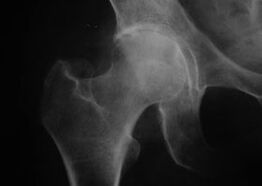

Coxathrose, arthrose de l'articulation de la hanche

Avec cette maladie, on observe un tableau clinique classique de l'arthrose.

Le premier symptôme de la coxarthrose est une gêne au niveau de l'articulation de la hanche après une activité physique.

Avec la coxarthrose progressive, la douleur augmente, des raideurs et une mobilité limitée apparaissent.

Les patients atteints d'une forme sévère de coxarthrose épargnent le membre atteint, évitent de marcher dessus et, à l'arrêt, choisissent les positions dans lesquelles la douleur est la moins ressentie.